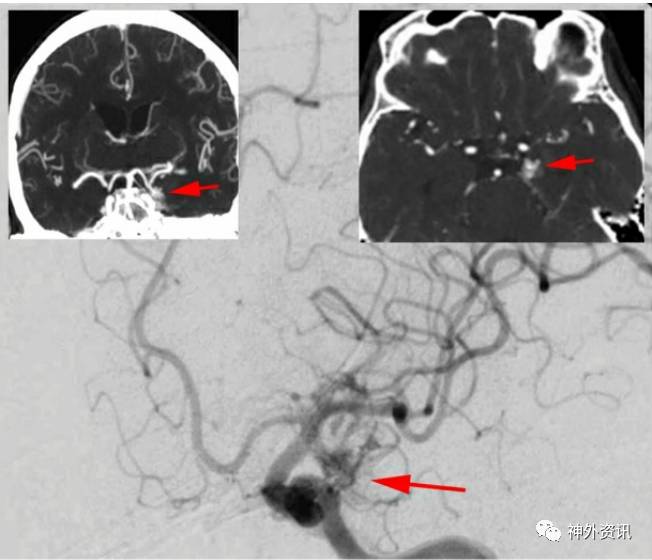

图8. 经斜位ICA血管造影显示左侧颞叶前内方的AVMs (上图)。CT血管造影图像(插图)定位AVMs。供血动脉源于颞叶前动脉、PCoA丘脑穿通支、海马动脉、颞叶后动脉、P2段。引流静脉是向内侧引流入基底静脉。术者通过经侧裂入路切除病变。可以看到颞前动脉紧贴AVMs经过(下图)。

图9. 充分的游离大脑侧裂,开放颈动脉池和基底池,将脉络膜前动脉,P2段轮廓化,断开AVMs内侧面的供血动脉。保留手术视野中的中脑穿支完好无损。注意引流静脉向后方越过钩回。MCA(吸引器下)显露。

图10. 来自颞前动脉(左)和M1主干(右)的供血血管被游离、切断。

图11. 其他源于P2、PCoA和脉络膜前动脉的供血血管也被切断。